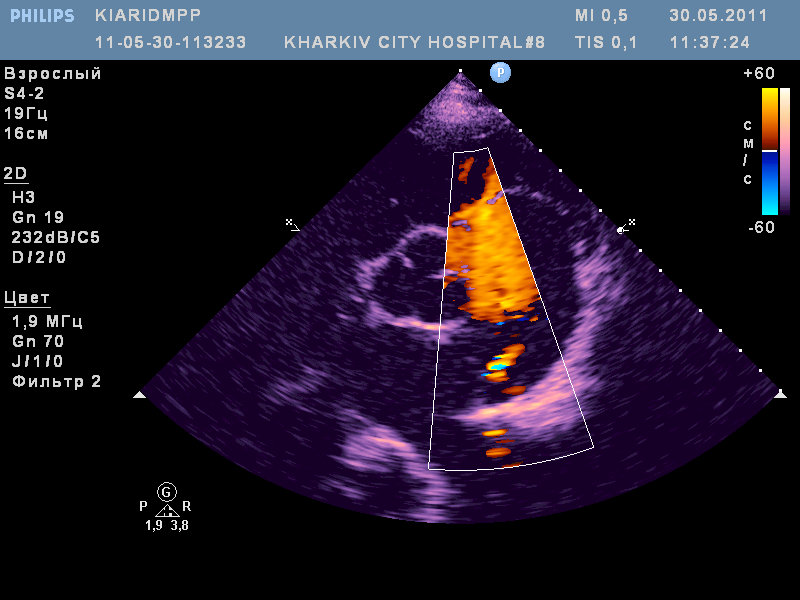

ВПС- высокий дефект межпредсердной перегородки (типа sinus venosus) с наличием аневризмы межпредсердной перегородки и сбросом слева-направо; сеть Киари.